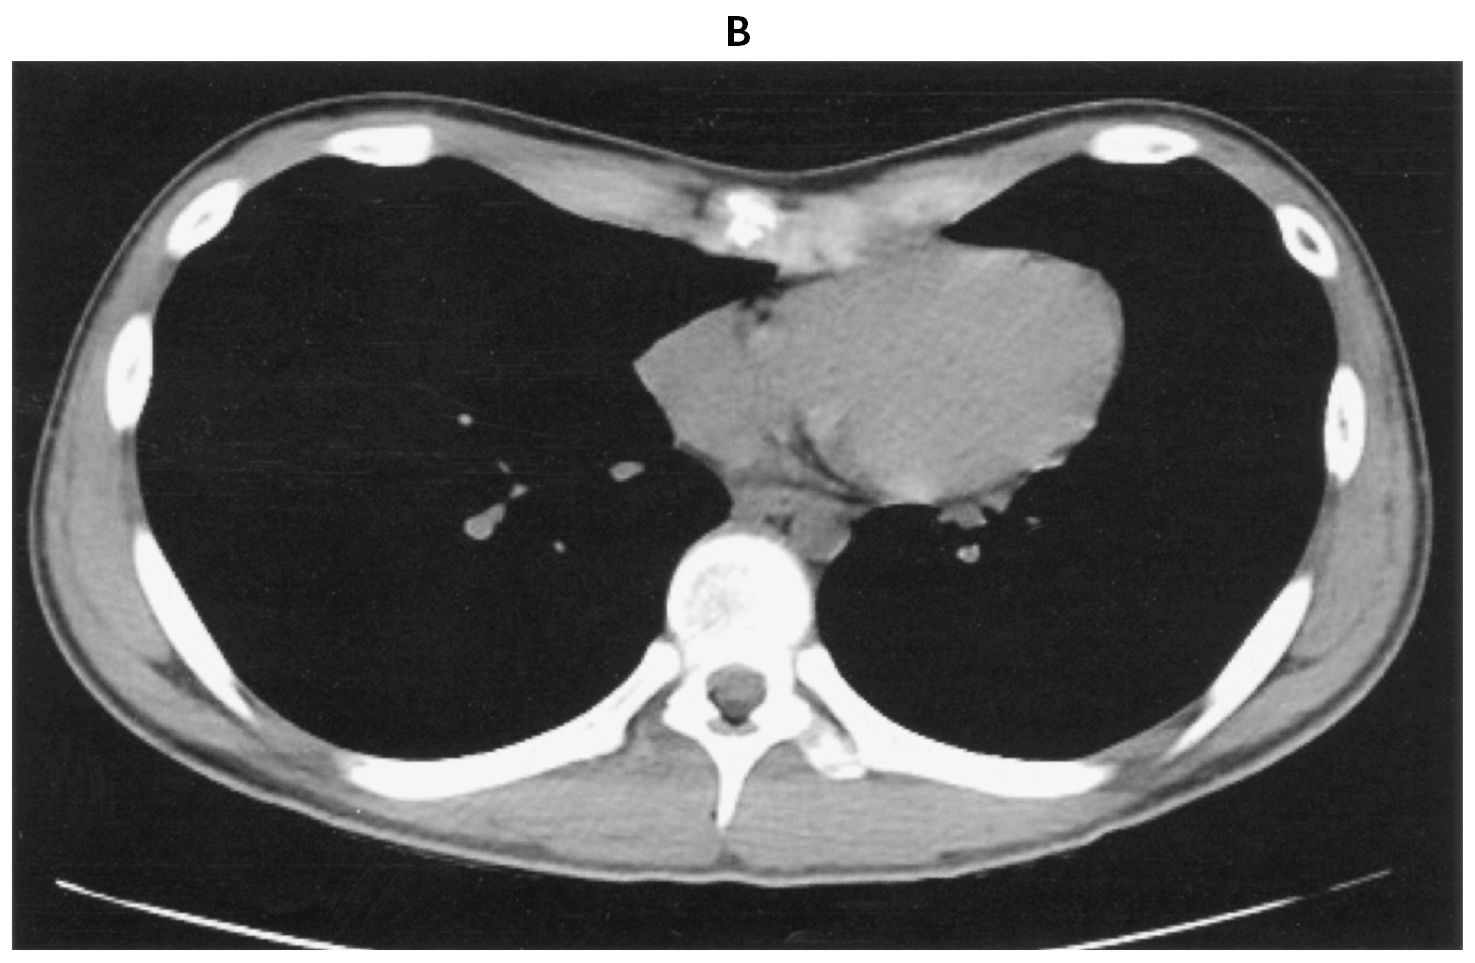

12歳の男児。胸郭の変形を主訴に来院した。学校で着替えの際に友人に胸の形について指摘され,本人が気にしている。自覚症状はない。意識は清明。身長158cm,体重40kg。体温36.6℃。脈拍60/分,整。血圧122/76mmHg。SpO2 96%(room air)。胸部エックス線写真(A)と胸部単純CT(B)とを下に示す。